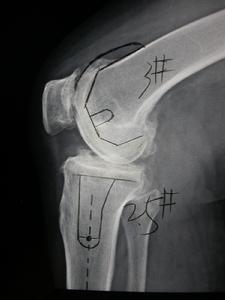

(四)頸椎小關節退行性變階段椎間盤、小關節、椎體形成一個三角形的支架結構,以穩定椎體間的關係,其功能是三位一體的。當椎間盤退行性變或椎體間關節受到損傷後,小關節的穩定性遭到破壞而出現病理性改變,關節囊變得鬆弛,導致關節突半脫位,形成損傷性關節炎。由於具備的變性,椎間關節間隙變窄和骨贅形成,椎間孔的前後徑及椎體上下間隙變小,刺激和壓迫脊神經和血管,影響局部血液循環和脊神經功能。由於脊柱呈垂直狀排列,越是下位的椎體關節,負重越大,因此也越易受累,也最早發生退變。所以我們常常看到,頸椎4-7最容易發生病變。

(1)椎間孔上下徑變窄:由於椎間盤退化變窄,上下椎體接近,故椎間孔的上下徑變窄。

(2)椎間孔前後徑變窄:由於頸椎的小關節面具有自前上向後下傾斜的解剖特點,故當椎間盤變性時,上面的椎體即沿著這個斜面向後滑而發生半脫位,造成椎間孔前後徑變窄而壓迫神經根,同時椎管前後徑亦變窄而壓迫脊髓,又由於椎間盤各部的變性程度不一,左右上下壓縮變扁的情況不盡相同,可以出現椎體偏歪鏇轉,棘突也相應地表現出左右偏歪。

五、腰椎小關節的退行性變椎間盤和小關節構成椎體間的一個三角形的支架結構,以穩定椎體間的關係。當腰椎退變或者椎體間關節受損後,小關節的穩定性遭到破壞而發生病理改變。出現腰椎關節穩定性下降,關節間隙狹窄和椎間孔狹窄,壓迫神經根而出現症狀。